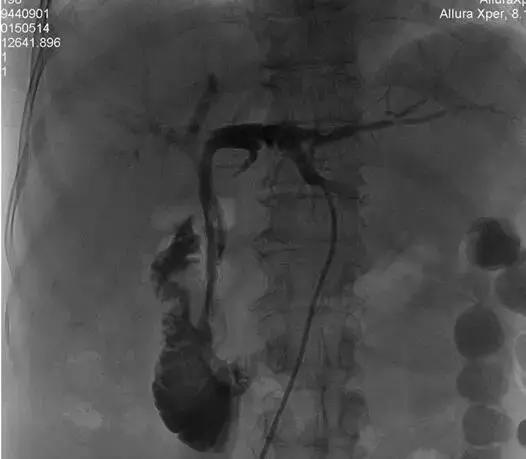

3、射频消融治疗及支架置入后造影再通